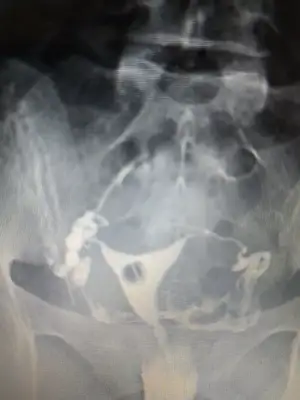

Onun hatlar karışık biraz. Çekim sonrası radyologun mesai saati bittiği için rapor yetişmemiş. Pazartesi alacak sonucunu. Kendi doktoru tüplerden birinde tıkanıklık var gibi konuşmuş ama başka doktorlara da göstermiş, basınçla açılmış demişler

pazartesi herşey sonuçlancak demek. Açılmıştır kuzum bak sorunun nerde olduğu anlaşıldı en azından en kısa zamanda gelecek beben